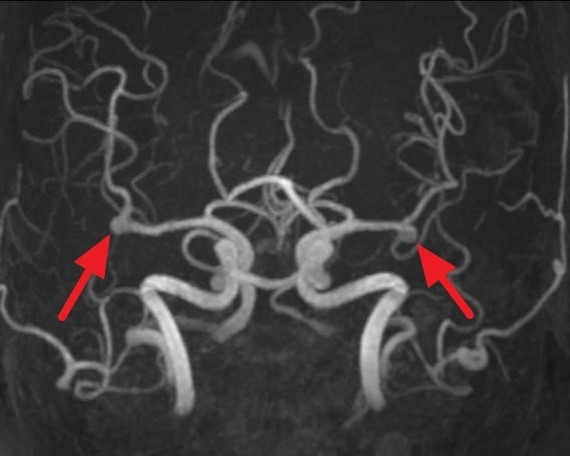

- 자기공명영상(MRI): 뇌의 상세한 영상을 제공하여 동맥류의 위치와 크기를 파악하는 데 도움이 됩니다.

- 뇌혈관 조영술: 혈관 내에 조영제를 주입하여 X선 촬영을 통해 동맥류의 정확한 모양과 위치를 확인합니다.